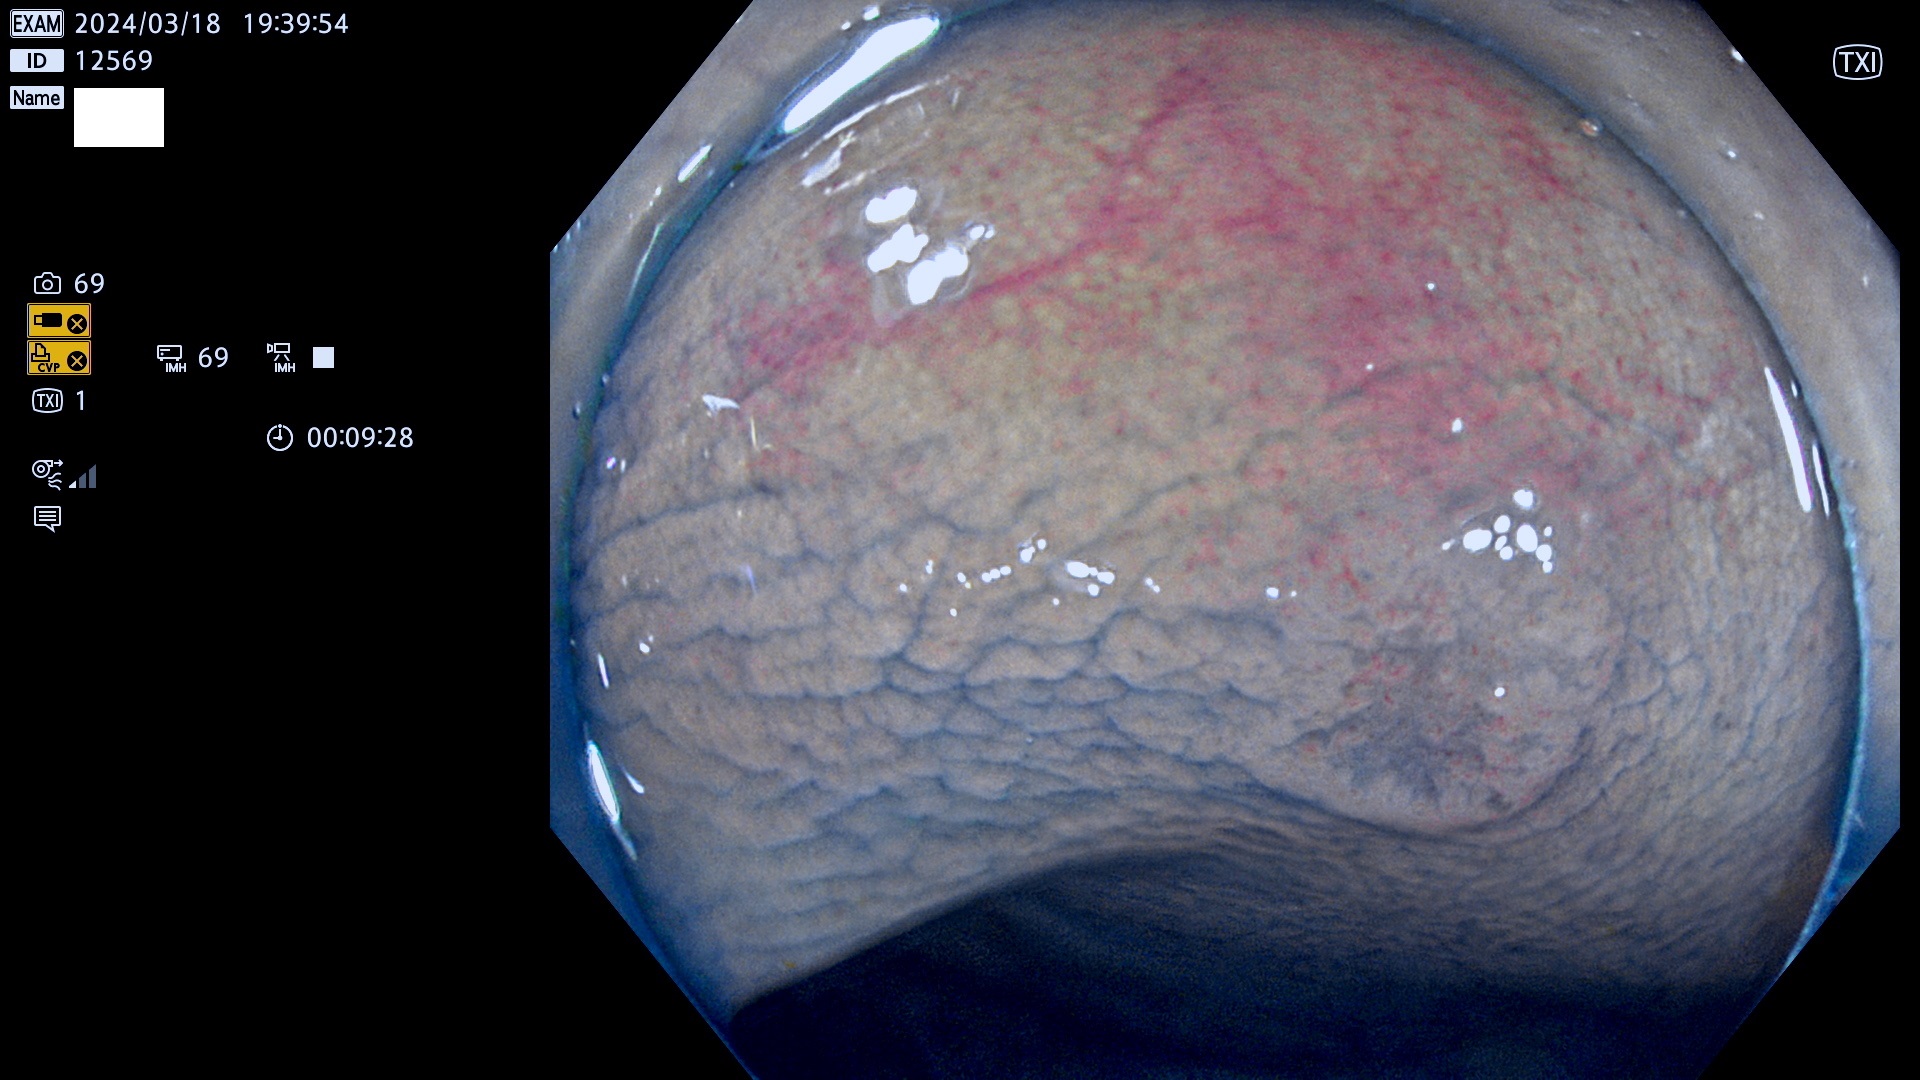

表面型腺腫(Flat Adenoma)の中で、完全に平坦な物をUb、陥凹している物をUcと呼びます。平坦隆起型(Ua)よりも、発見が難しく危険な病変です。

抽出の対象期間 2024年3月14日(木)〜3月18(月)の5日間(55件の検査)12件 (12/55=22%)